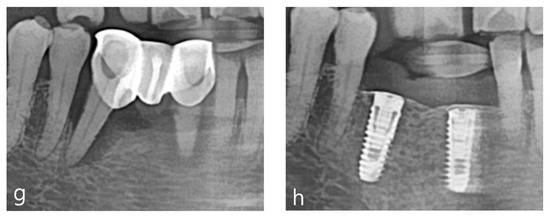

Clinical Application of rhBMP-2 and Three-Dimensinal Preformed Titanium Mesh with Allograft and Xenograft for Peri-Implant Horizontal and Vertical Bone Augmentation–A Narrative Review with Technical Report

2. Materials and Methods

3. Results